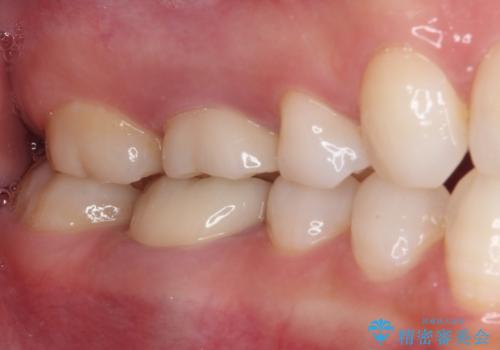

- 奥歯の銀歯が外れたことをきっかけに、全ての銀歯をセラミックに替えたいとのことで来院された患者様です。

第一大臼歯4本と、メタルインレーが装着されている2歯をセラミッククラウンならびにセラミックインレーにて補綴治療・修復治療を行うこととしました。

口腔内から、土台も含め銀歯がなくなったことでメタルフリーとなりました。